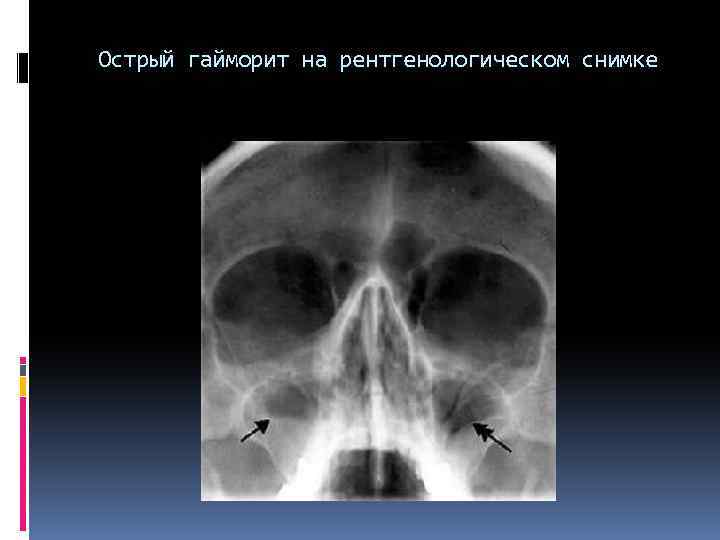

Острый гайморит на рентгенологическом снимке Острый гайморит на рентгенологическом снимке